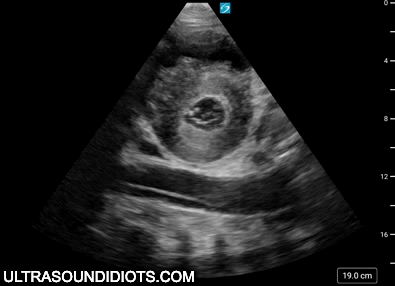

This website is designed to be an open educational resource for the clinical application of point-of-care ultrasound.